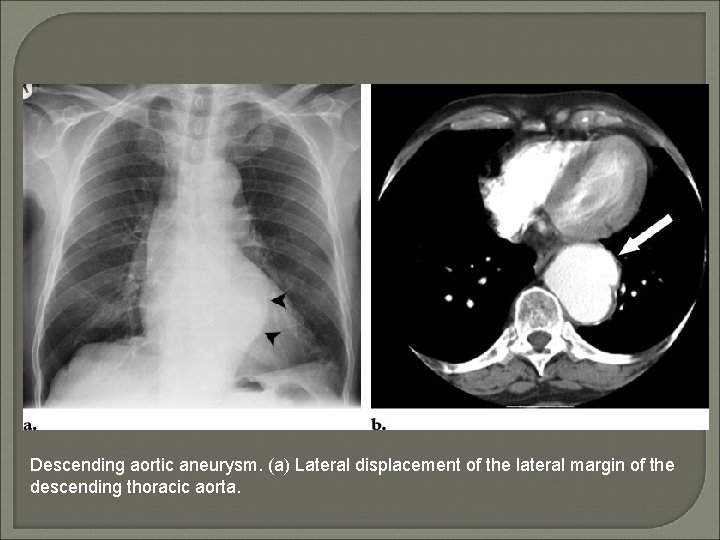

Descending aortic aneurysm. (a) Lateral displacement of the lateral margin of the descending thoracic aorta.